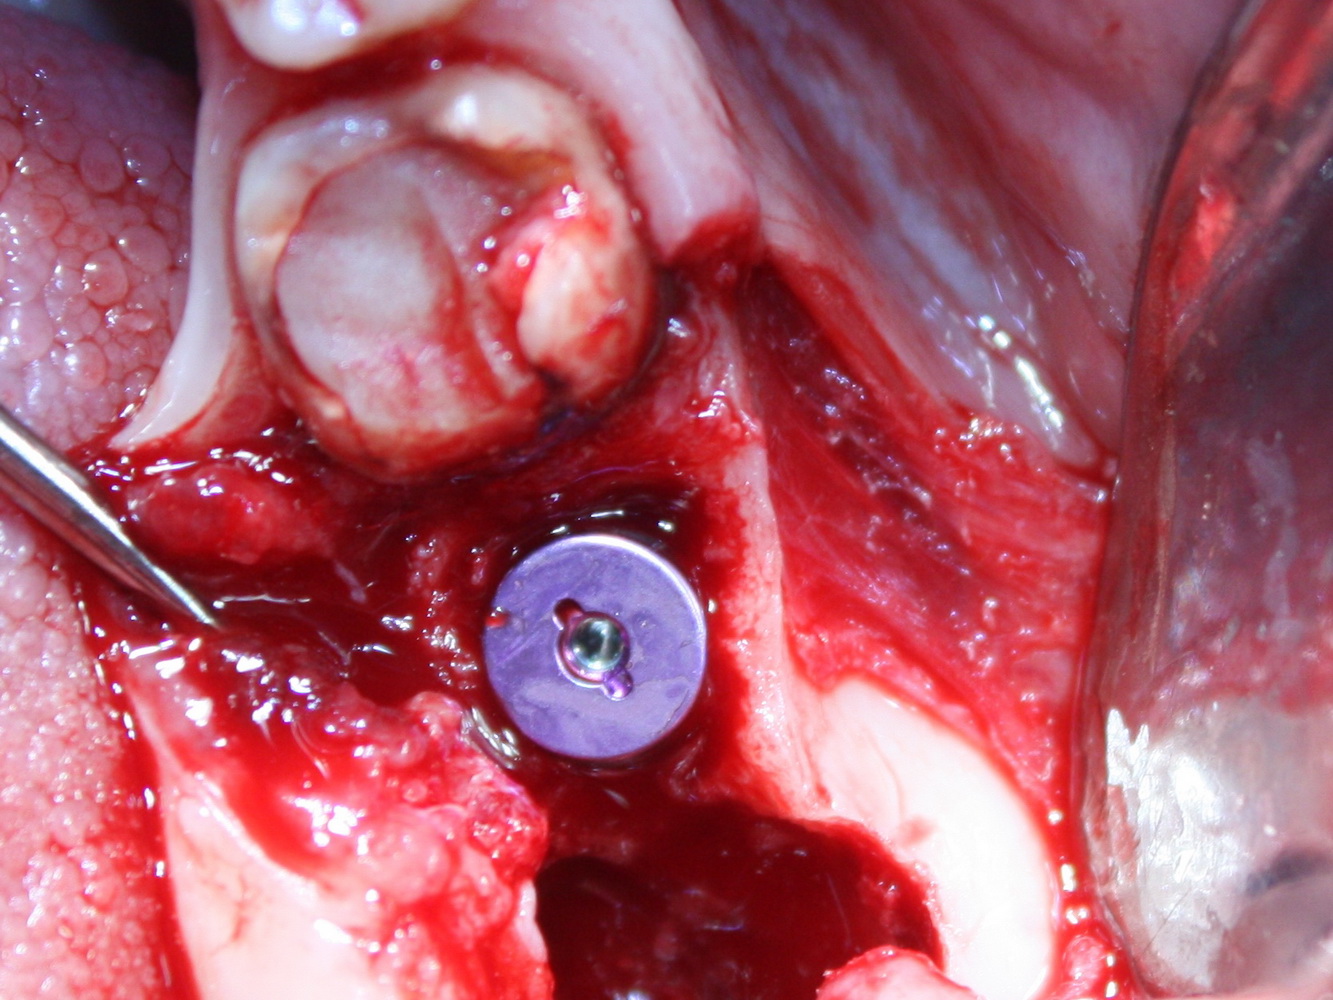

Немедленная имплантация — оптимальное решение в любой клинической ситуации